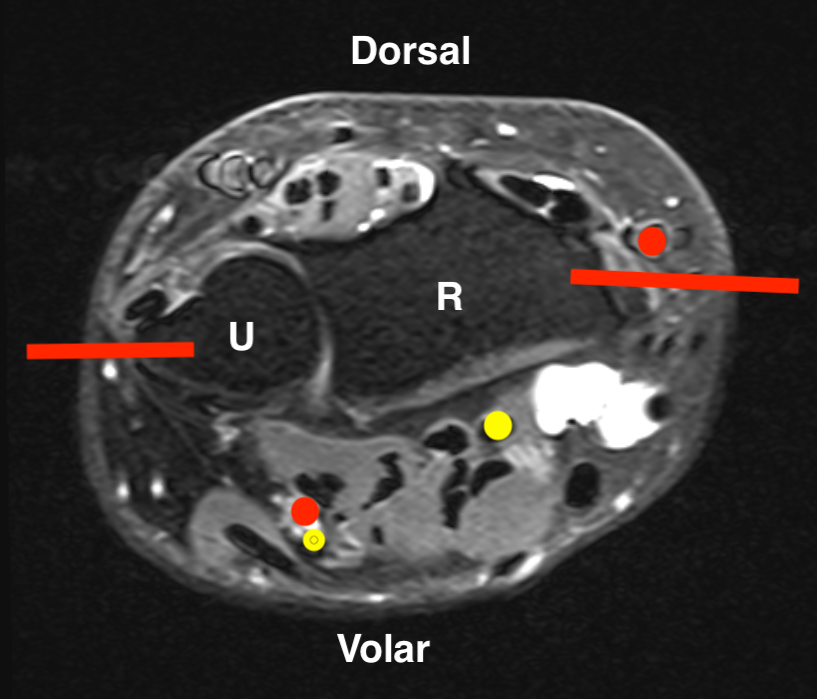

Radius and Ulna

Radius Ulna

Proximal - posterolateral Olecranon - direct posterior

Shaft - direct lateral Ulna shaft - direct medial

Distal radius - direct lateral

Ulna tumourUlna biopsy

GCT distal radiusDistal radius biopsy